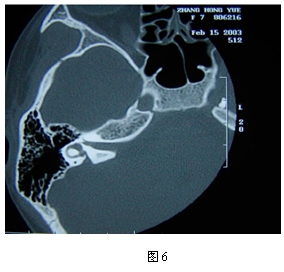

老年性聽力減弱的診斷

根據老齡聽力減弱史,鼓膜一般正常,純音測聽為平坦或下降型聽力曲線,有音衰,語言識別率明顯低下,診斷不難。